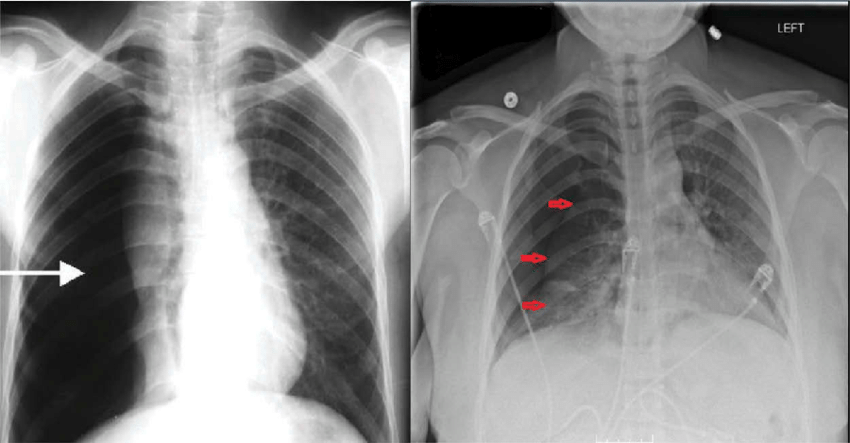

- 정의: 폐 또는 흉강 내에 공기가 채워지는 상태

- 발생 원리: 흉강 내 음압 공간에 공기가 유입되면서 발생

- 치료 방법: 흡인 또는 흉관 삽입